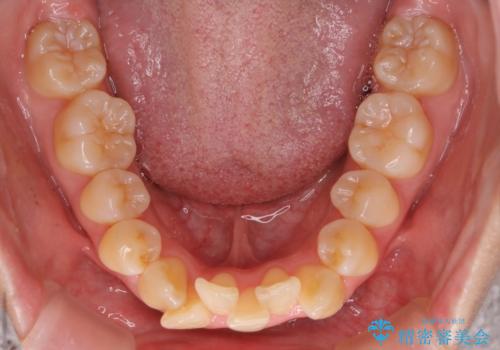

- 前歯が出ていることと、下の歯のがたがたで歯磨きがしにくいことを主訴に来院されました。

マウスピース矯正の希望があり、ワイヤーリカバリの可能性を伝えたうえでインビザライン抜歯矯正を行っています。